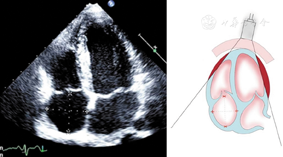

(1)胸骨旁左心室长轴切面(图1图2图3)

胸骨旁左心室长轴切面引导2a区M型超声心动图,显示收缩末期和舒张末期室间隔厚度、左心室内径和左心室后壁厚度测量方法

图2

胸骨旁左心室长轴切面,显示二维超声心动图舒张末期左右心室壁厚度、室间隔厚度和左右心室内径测量方法